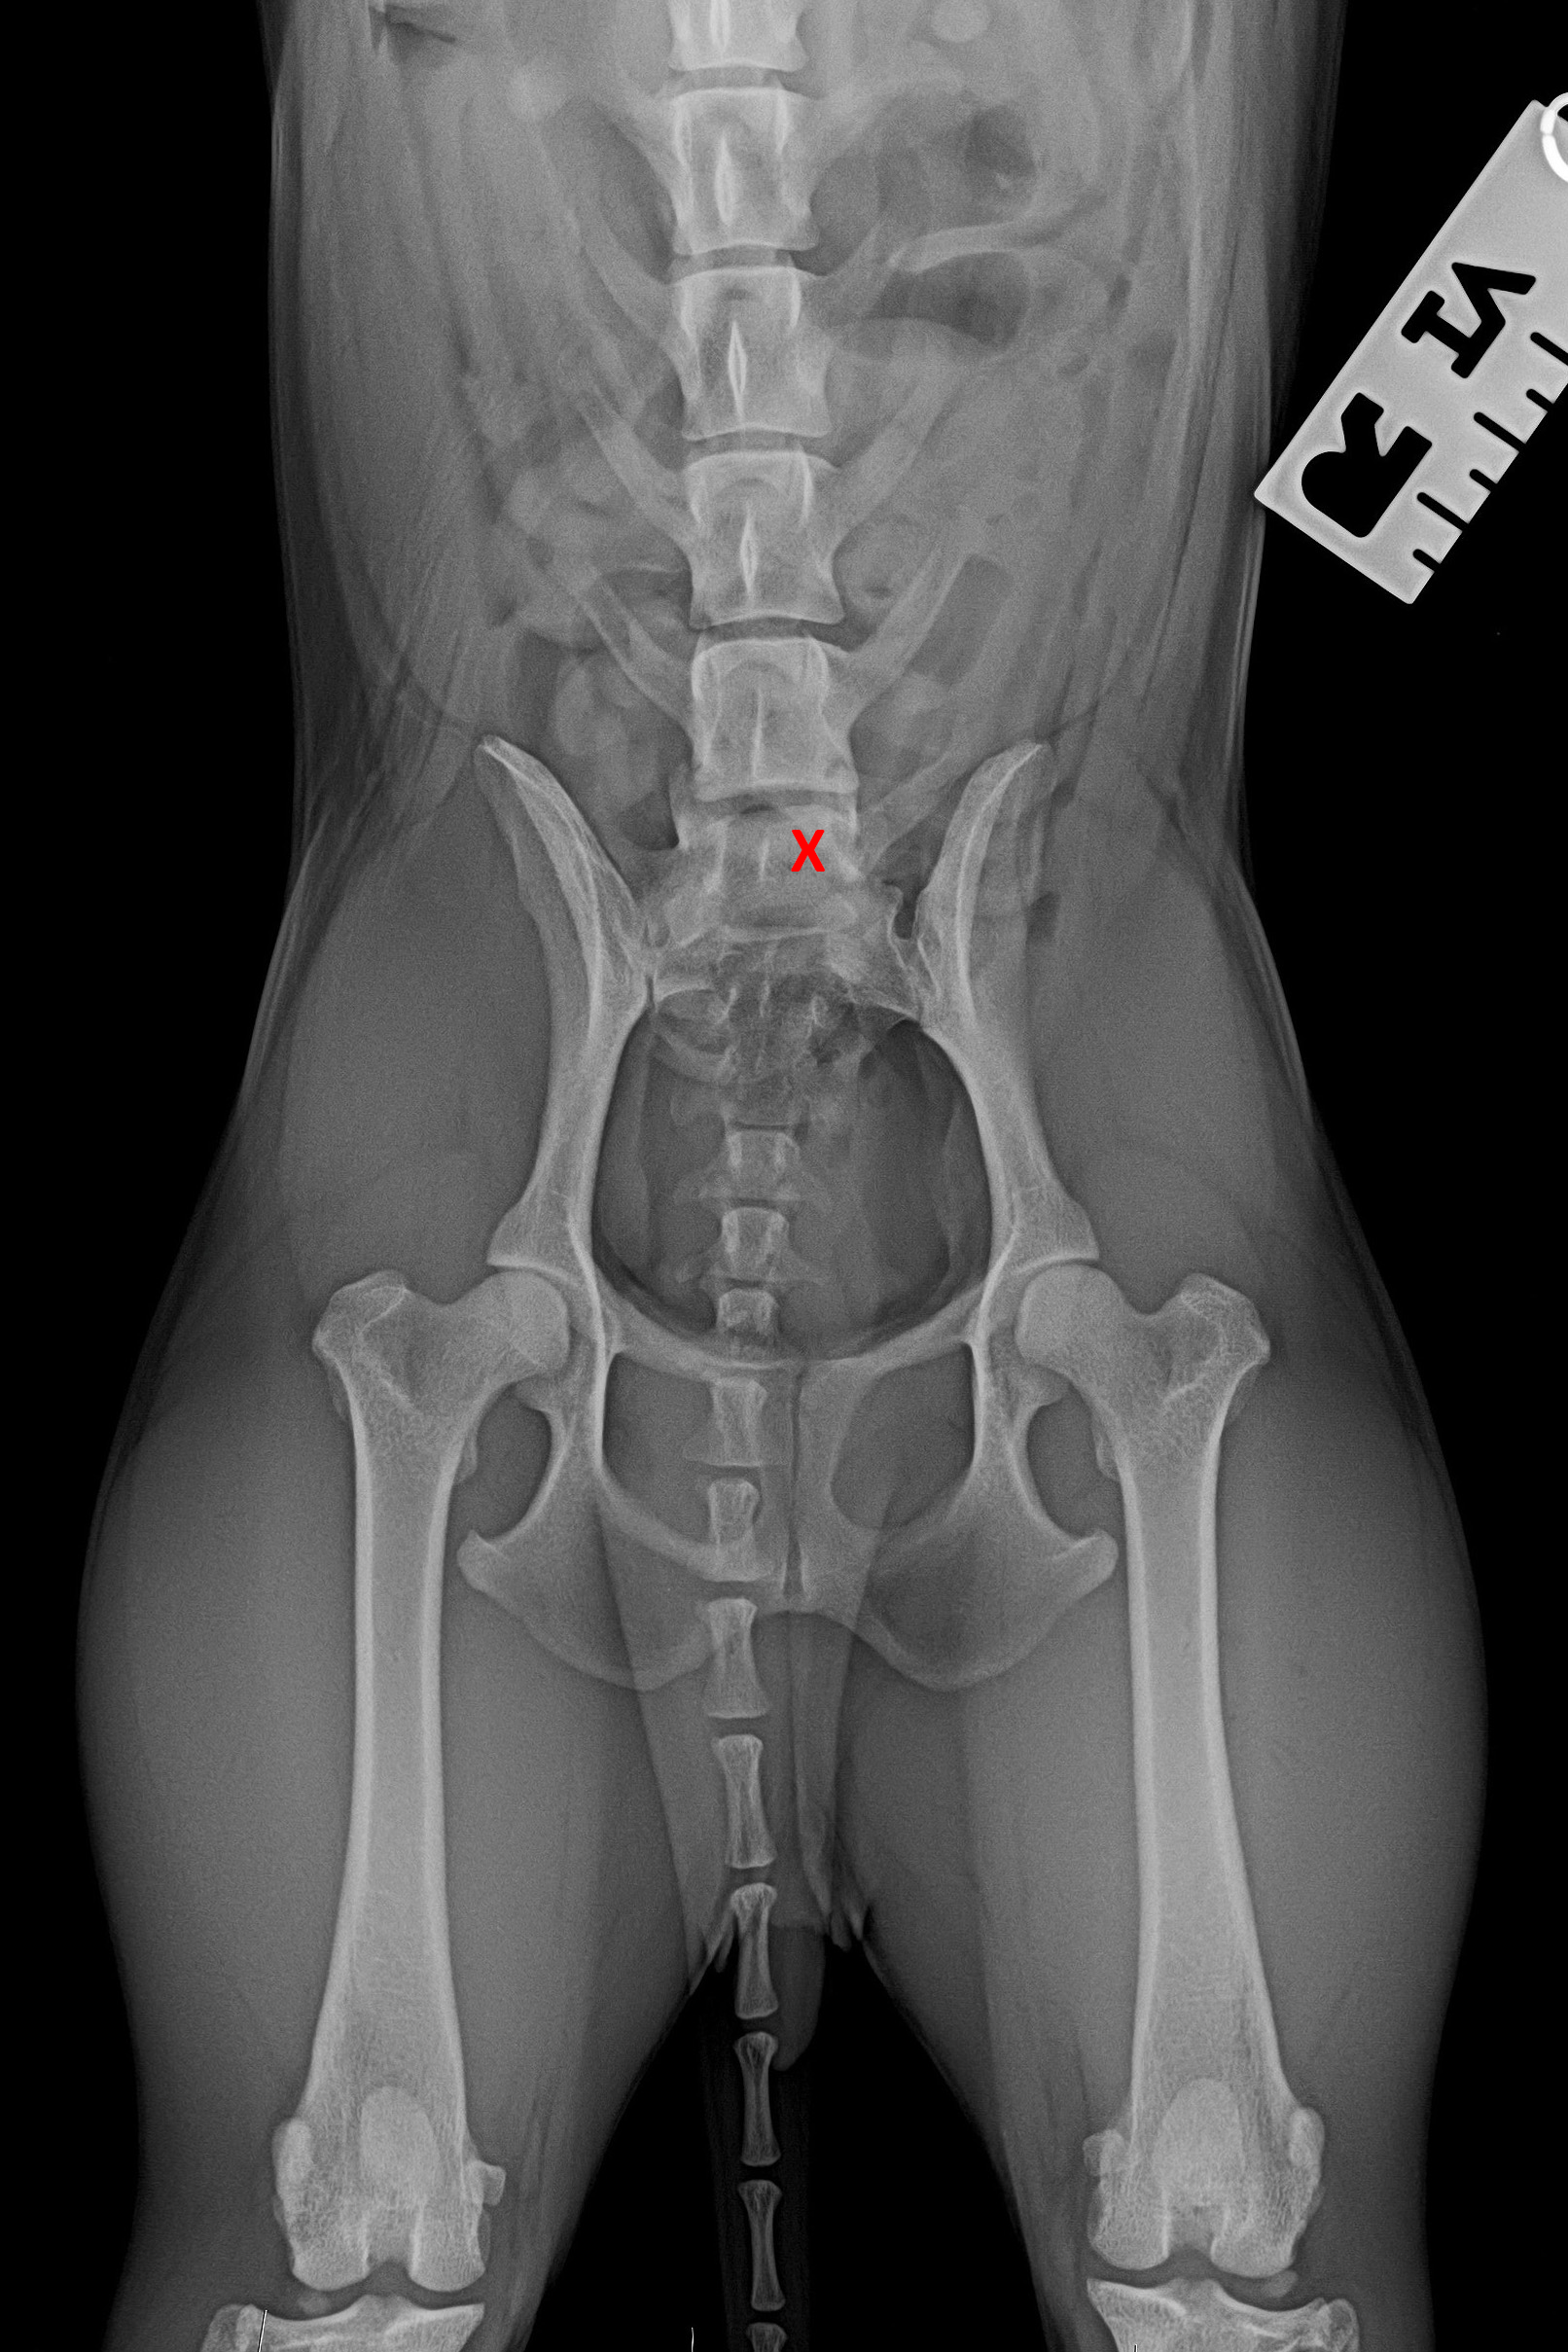

(3) 7 měsíců VD 1

(3) typ 3 po korekci polohy pánve

(4) 7 měsíců VD 2

(4) typ 3 po korekci polohy pánve 2